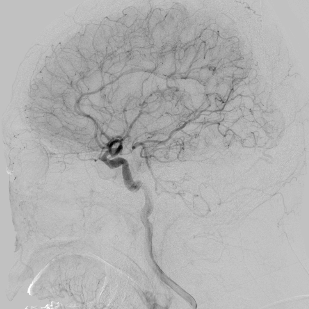

相逢就是缘,有求必全力以赴。立即进行全面评估,CTA和MRI发现颅内多发脑梗塞,脑干为重,双侧椎动脉颅内段基本看不到了,而进一步的DSA造影更为糟糕,左侧椎动脉的颅内颅外段直接全程完全闭塞,右侧颅外剩下一个小尾巴在血液中摇摇欲坠……,诺大的后循环仅仅靠纤细的后交通动脉从前循环借点血液过来,勉强续命,仅仅靠这点前循环的救急,可谓“杯水车薪”,不是“长久之计”,于是决定开通右侧闭塞的椎动脉(颅内+颅外,主要集中在V3+V4段)。

微导管继续超过去,轻轻造影,开通的路径隐约返流闪现,立即改变策略,逆向铺路,开通成功。

术后查房,患者头晕消失,双侧听力基本恢复,整个手术时间历时7个小时,过程是艰难的,结果是欣慰的~~~